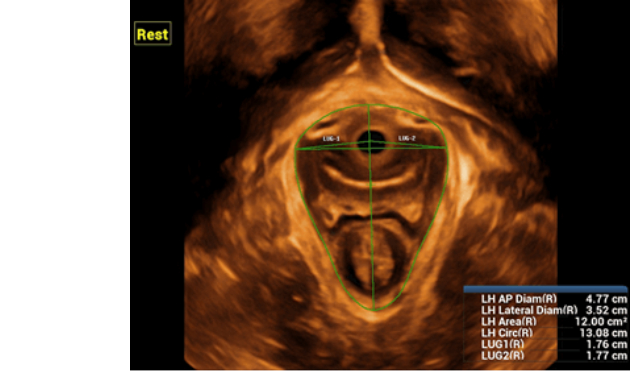

Realizing the increasing importance of ultrasound diagnosis on pelvic floor disorders, DC-80 with X-Insight provides a new solution to greatly simplify the operation procedures, and to minimize the exam time for a standardized evaluation on pelvic floor. With extremely simple user-interaction, it generates a standard coordinate system and automatically provides all related measurements within a few seconds.